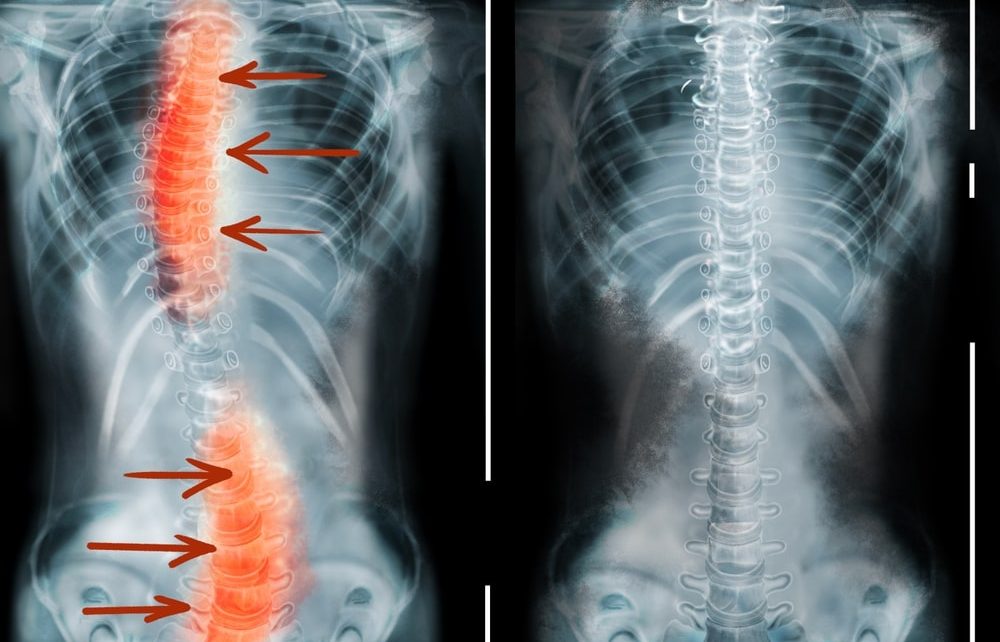

Scoliosis, a condition characterized by an abnormal lateral curvature of the spine, is primarily understood through the lens of orthopedics. For many, the focus is on spinal angles, bracing, or surgical intervention. However, for those living with the condition, the impact is often as visual as it is structural. The skeletal shifts associated with scoliosis frequently result in noticeable physical asymmetries: one shoulder sitting higher than the other, a prominent shoulder blade, an uneven waistline, or a “rib hump.”

Scoliosis does not just affect the “internal” spine; it reshapes the entire torso. As the vertebrae rotate and curve, they take the attached musculature and overlying skin with them.